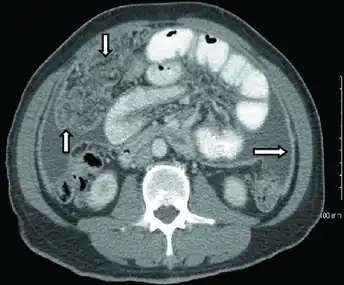

CT scan of peritoneal tuberculosis, a form of extrapulmonary tuberculosis. The omentum and peritoneal surfaces are thickened (arrows).<ref name="AkceBonner2014">Akce M, Bonner S, Liu E, Daniel R (2014). "Peritoneal tuberculosis mimicking peritoneal carcinomatosis". Case Reports in Medicine. 2014: 436568. doi:10.1155/2014/436568. PMC 3970461. PMID 24715911.

In active pulmonary TB, infiltrates or consolidations and/or cavities are often seen in the upper lungs with or without mediastinal or hilar lymphadenopathy or pleural effusions ( tuberculous pleurisy). However, lesions may appear anywhere in the lungs. In disseminated TB a pattern of many tiny nodules throughout the lung fields is common - the so-called miliary TB. In HIV and other immunosuppressed persons, any abnormality may indicate TB or the chest X-ray may even appear entirely normal.